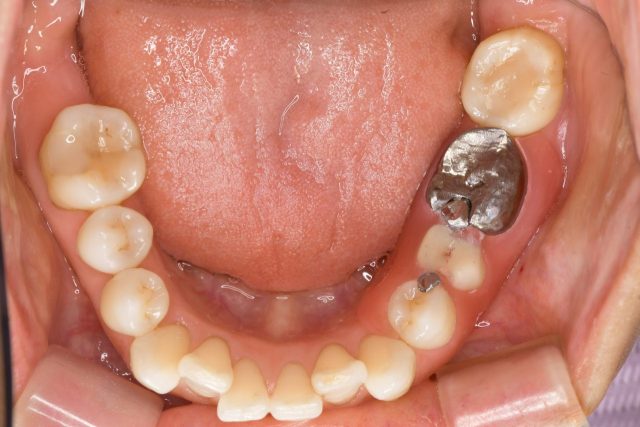

治療後

【治療後】

金属の留め具がないため、自然な仕上がりに